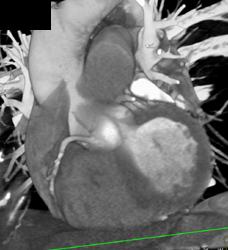

SVC Thrombus With Collaterals. Tumor Invades the SVC